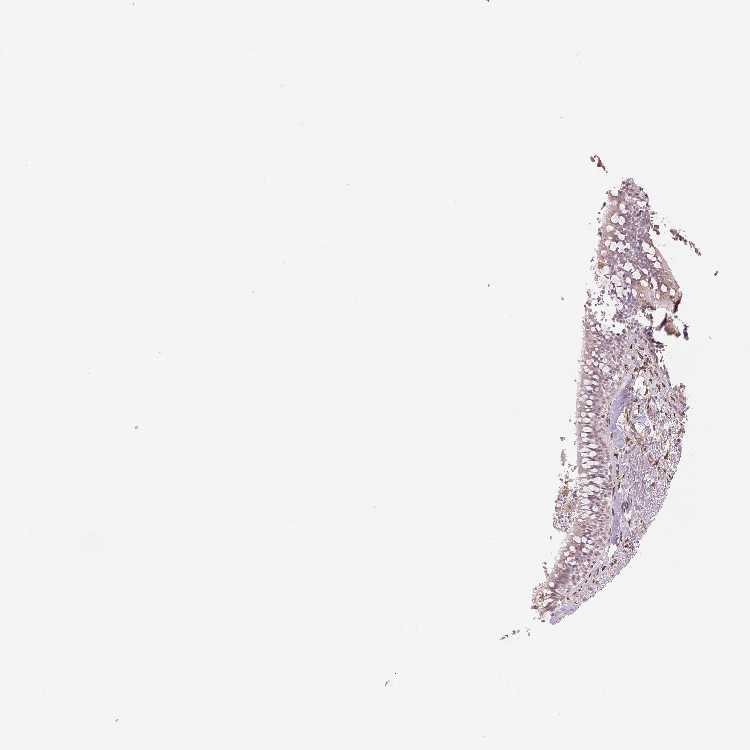

SOFT TISSUE 1 - Antibody stainingi

Antibody staining in the annotated cell types in the current human tissue is reported as not detected, low, medium, or high, based on conventional immunohistochemistry profiling in selected tissues. This score is based on the combination of the staining intensity and fraction of stained cells.

Each image is clickable and will lead to virtual microscopy that enables deeper exploration of all samples and also displays staining intensity scores, fraction scores and subcellular localization as well as patient and tissue information for each sample.

Antibody HPA051171Antibody HPA057021

Chondrocytes Not detectedMedium

Fibroblasts LowHigh

Peripheral nerve Not detected-